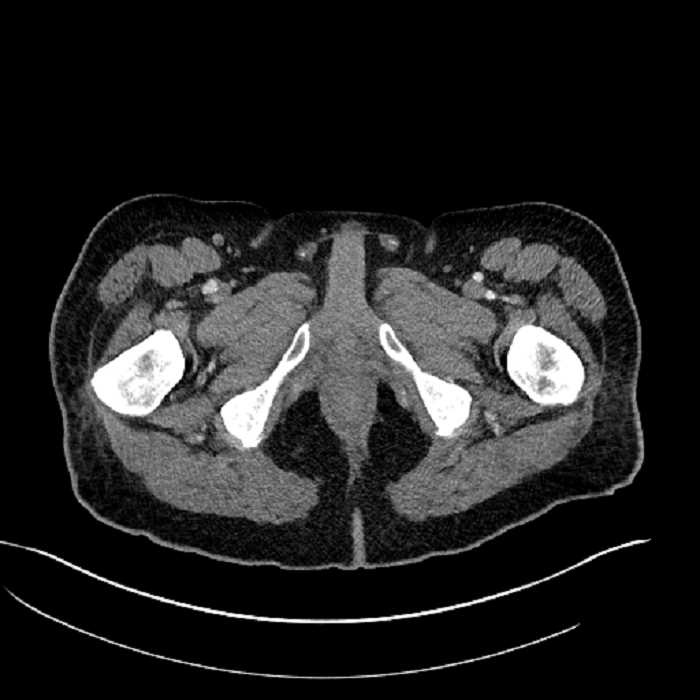

• High grade stenosis of the left common iliac artery, with the left internal and external iliac arteries remaining patent

High grade stenosis of the left common iliac artery. The left external and internal iliac arteries are patent.

Hepatic abscess showing the double target sign with low density internally surrounded by a thin inner enhancing rim (red arrow) and ill-defined outer low density rim (yellow arrow). Blue arrow indicates an internal septation. Red arrows: additional smaller subcapsular abscesses. Red arrow: focal contained perforation associated with diverticulitis.